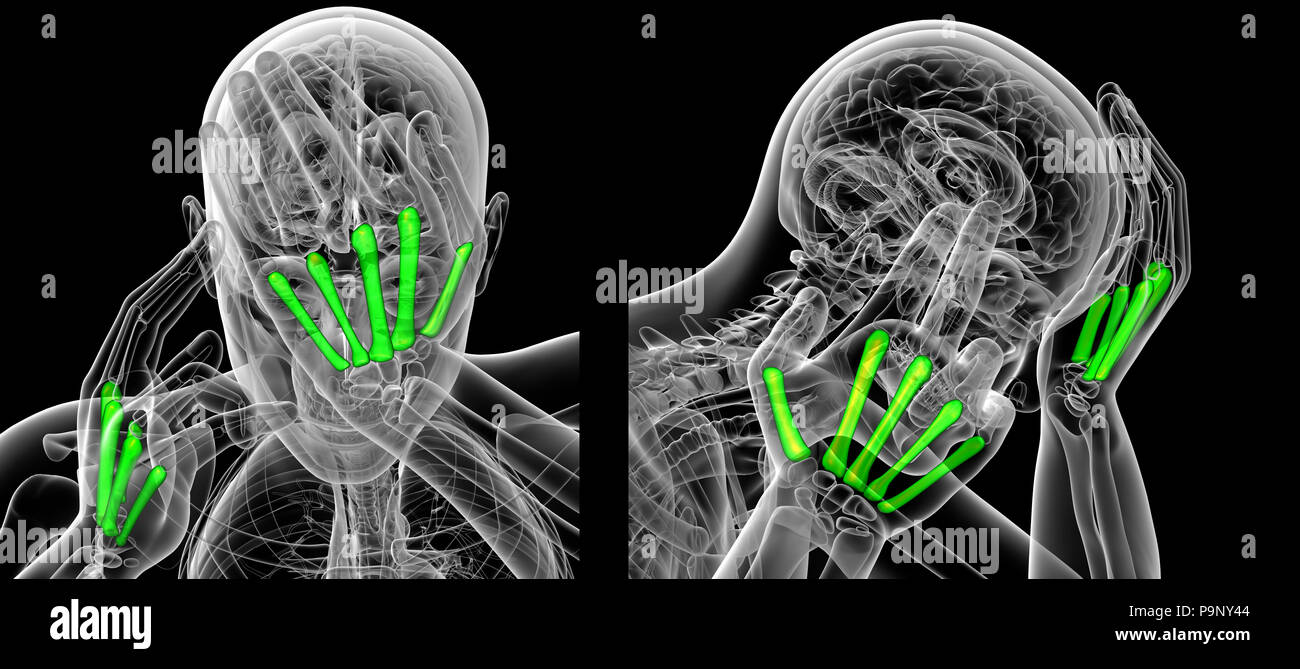

3d rendering of metacarpal Stock Photohttps://www.alamy.com/image-license-details/?v=1https://www.alamy.com/3d-rendering-of-metacarpal-image212538596.html

3d rendering of metacarpal Stock Photohttps://www.alamy.com/image-license-details/?v=1https://www.alamy.com/3d-rendering-of-metacarpal-image212538596.htmlRFP9NY44–3d rendering of metacarpal

3d rendering illustration of metacarpal Stock Photohttps://www.alamy.com/image-license-details/?v=1https://www.alamy.com/3d-rendering-illustration-of-metacarpal-image212538578.html

3d rendering illustration of metacarpal Stock Photohttps://www.alamy.com/image-license-details/?v=1https://www.alamy.com/3d-rendering-illustration-of-metacarpal-image212538578.htmlRFP9NY3E–3d rendering illustration of metacarpal

3d rendering of metacarpal Stock Photohttps://www.alamy.com/image-license-details/?v=1https://www.alamy.com/3d-rendering-of-metacarpal-image212538382.html

3d rendering of metacarpal Stock Photohttps://www.alamy.com/image-license-details/?v=1https://www.alamy.com/3d-rendering-of-metacarpal-image212538382.htmlRFP9NXTE–3d rendering of metacarpal